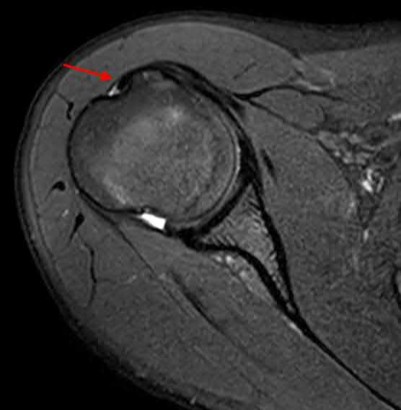

Question 11:

A poly-trauma patient presents hemodynamically unstable with an anteroposterior compression (APC-III) pelvic ring injury. A circumferential pelvic binder is requested to reduce pelvic volume and control hemorrhage. To be anatomically effective, the binder must be centered precisely over which of the following landmarks?

Correct Answer: Greater trochanters

Explanation:

For optimal mechanical advantage and effective reduction of an 'open book' pelvic fracture (APC type), a pelvic binder must be applied directly over the greater trochanters of the femurs. Applying it higher, such as over the iliac crests, is a common error that fails to adequately close the pelvic ring and can paradoxically open the true pelvis.